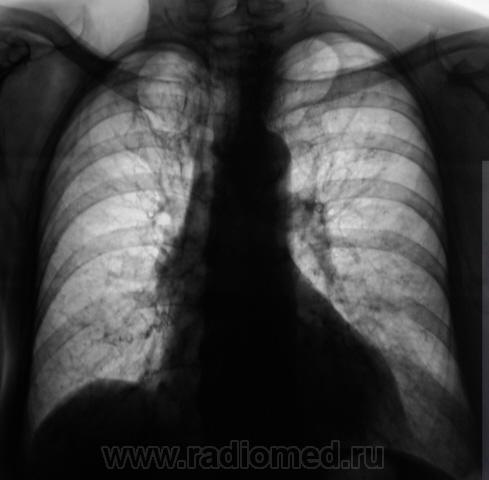

Срава - локальный фиброз и мелкие плотные очаги, слева - плотные очаги; все - старое, нового не наблюдается, как по мне.